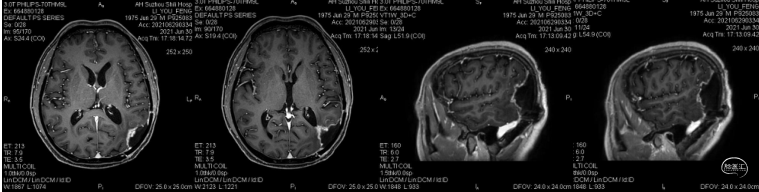

患者为中年男性,因“间断性头痛2月,加重1周”于2020年4月30日入院。入院时神经系统体征(-)。术前诊断为左顶枕叶胶质瘤。